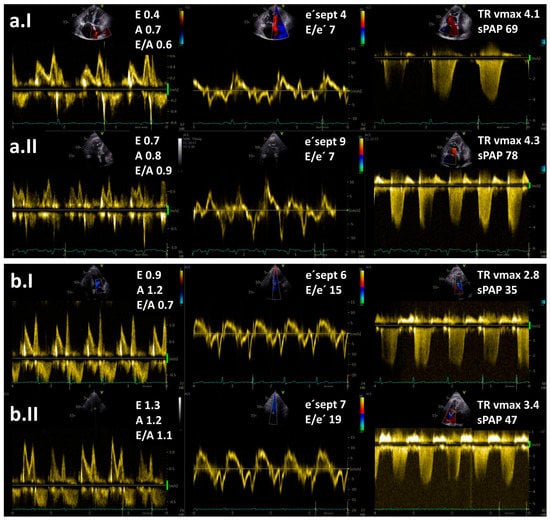

In spite of the above-mentioned data, the diagnostic value of the stress tests during echocardiography to distinguish between PH subtypes is currently uncertain due to the lack of prospective data, especially regarding its use to identify cases of combined post- and pre-capillary PH. Based on the data from the literature, exercise echocardiography is considered abnormal if the average E/e′ ratio at peak stress increases to ≥15, with or without a peak TR velocity >3.4 m/s (Figure 2) [10,11,12]. An increase in TR velocity only should not be used to diagnose post-capillary PH because it might be a normal hyperdynamic response to exercise with increased pulmonary blood flow in the absence of LV diastolic dysfunction [31].

Figure 2.

Resting (I) and exercise stress echocardiography (II) in two patients with pulmonary hypertension (PH): (a) a patient with pre-capillary PH and (b) a patient with post-capillary PH. Maximal tricuspid regurgitation velocity (TR vmax) is elevated in both patients. Note an increase in E/e′ ratio at low-level exercise from 15 to 19 in a patient with post-capillary PH but no increase in a patient with pre-capillary PH. Legend: sPAP—systolic pulmonary arterial pressure.